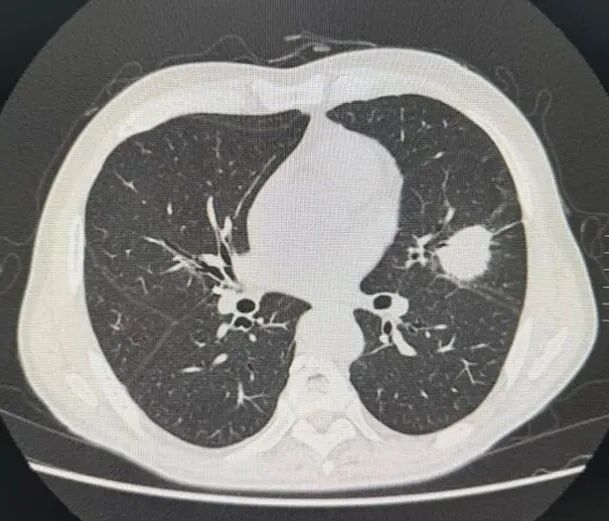

患者男性73岁;既往12年前行肝癌切除术;本次当地医院体检行胸部CT发现左上肺占位,大小约3.3 cm✖️2.7 cm。

PET-CT全身评估:左肺上叶实性结节FDG代谢异常增高,考虑恶性病变;

利用CT引导下肺病损穿刺活检,明确病理为:浸润性腺癌。

完善评估患者cT2aN0M0 IB期,符合手术指征遂行“胸腔镜下左肺癌根治术+淋巴结清扫”。术后病理揭示患者肿瘤学特征:低分化腺癌;STAS(+);ALK融合突变;淋巴结转移包括:第4组、5组、11组、12组。